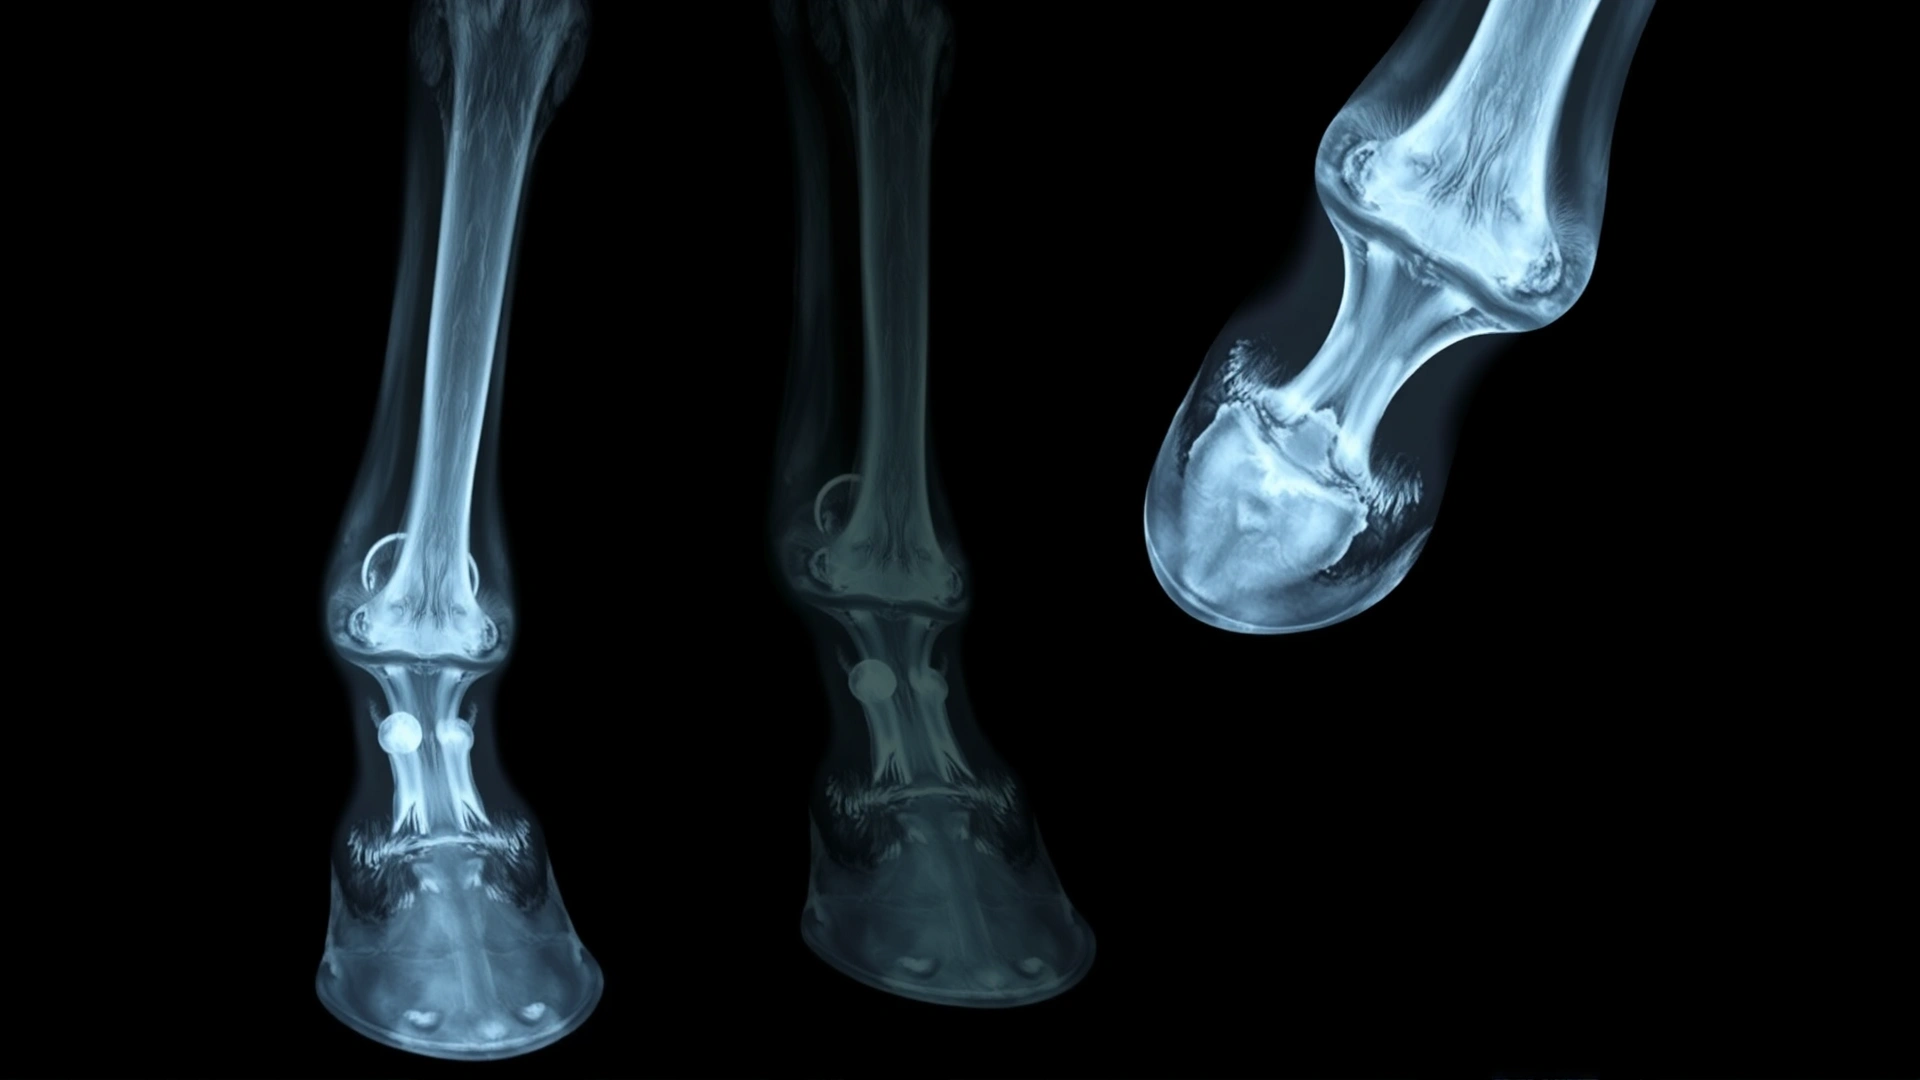

- الأشعة السينية (X-ray): أفضل وسيلة لتحديد موقع وحجم الكيراتوما بدقة، إذ تُظهر تجويفًا دائريًّا أو بيضاوي الشكل في عظم الحافر يمثل منطقة الضغط.

- التصوير بالرنين المغناطيسي (MRI): يُلجأ إليه في الحالات المعقدة لتقييم الأنسجة الرخوة والجدار القرني بشكل أوضح.